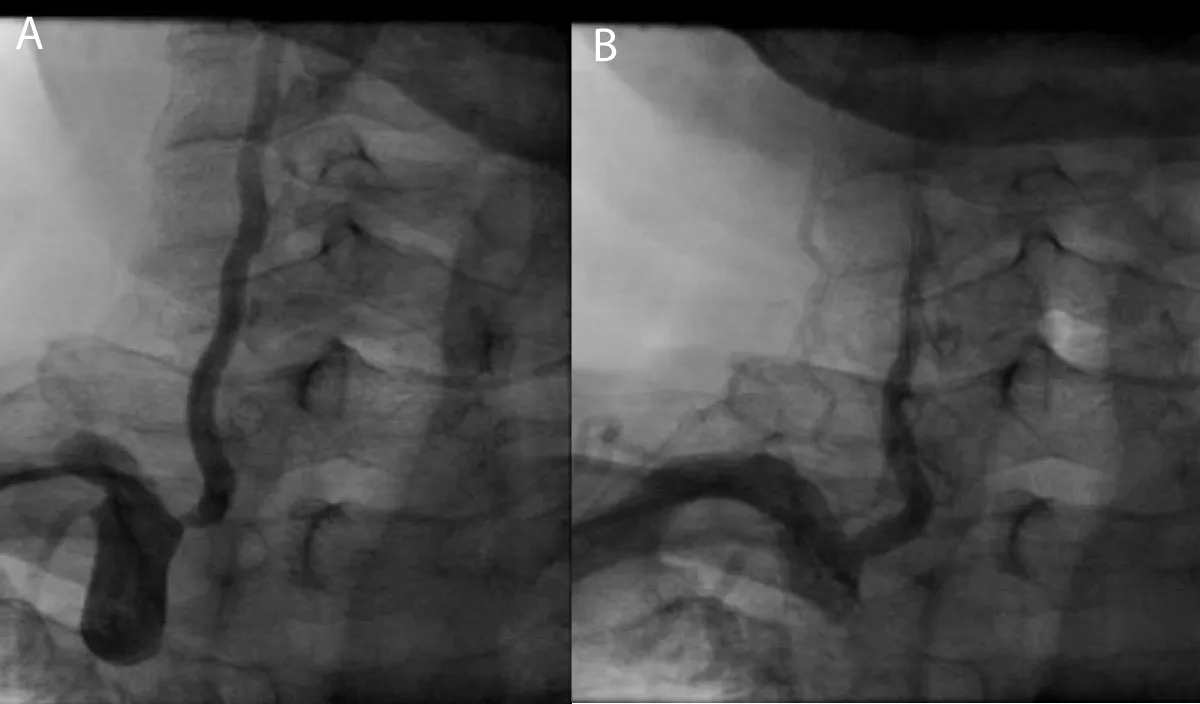

A 67-year-old male patient wasn’t known case of any chronic illness, and presented with chest tightness radiating to both shoulders associated with sweating and nausea for 2 hours, on examination: Patient was conscious, oriented, sweaty, not in respiratory distress and his blood pressure: was 150 / 90 mmHg, Temperature: 37 °C, Heart rate: 80 bpm O2 saturation: 99%, Electrocardiography (ECG) was done at the Emergency department which was showing ST-segment Elevation in V1 - V6 leads with reciprocal changes in inferior leads II, III, AVF. Aspirin 300 mg, clopidegrel 600 mg and morphine 3 mg were given then according to AL-Shifa Hospital protocol, patient was transferred to cardiac catheterization department for primary Percutaneous Coronary Intervention (PCI), then coronary angiography showed total occlusion of proximal left anterior descending artery (LAD), other vessels were normal, So coronary wire passed freely in LAD and resolute integrity stent 3 x 18 mm (drug eluting stent) was deployed successfully in proximal LAD, during that patient developed sudden onset of left upper limb and left lower limb weakness, National institute of health scale score (NIHS) score 8, So cerebral angiography was done and it was showing TICI Flow III with residual thrombus in MCA (Figure 1), by microcatheter in right middle cerebral artery, intra-arterial alteplase 8 mg was given, then weakness completely was resolved after 10 min with no residual neurological deficit, after that patient was transferred to coronary care unit for 2 days and discharged with good general condition and mRS (0), then he was maintained on aspirin 100 mg daily, clopidogrel 75 mg daily, atorvastatin 80 mg daily and bisoprolol 5 mg daily. Echocardiography: suggested apical hypokinesia with 1.2 x 1.1 mm thrombus, impaired left ventricular ejection fraction: 36%. Follow-up after 3 months was done and the patient had mRS 0.

Figure 1: A- coronary angiography, total occlusion of proximal LAD, B- after stent deployment in proximal LAD, C-cerebral angiography, TICI Flow III with residual thrombus in MCA.